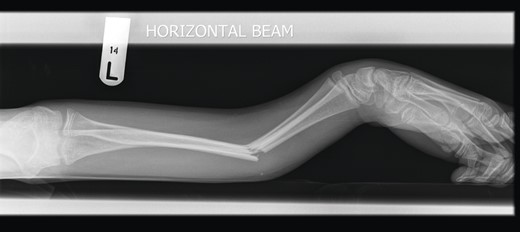

A 12-year-old male patient sustained a closed midshaft both-bone forearm fracture of their non-dominant arm from a fall on a trampoline (Figs 1 and 2). Anatomical reduction was achieved with a manipulation under anaesthesia (MUA), but it was noticed that there was a mechanical block to extension of the ring finger. The radius and ulna were therefore approached through separate incisions and it was discovered that the FDP was entrapped at the ulna fracture at the level of the musculotendinous junction. Following release the fingers regained a full range of motion and the patient went on to heal without further complication (Figs 3 and 4).

Three months post-operative lateral radiograph showing radiological union.